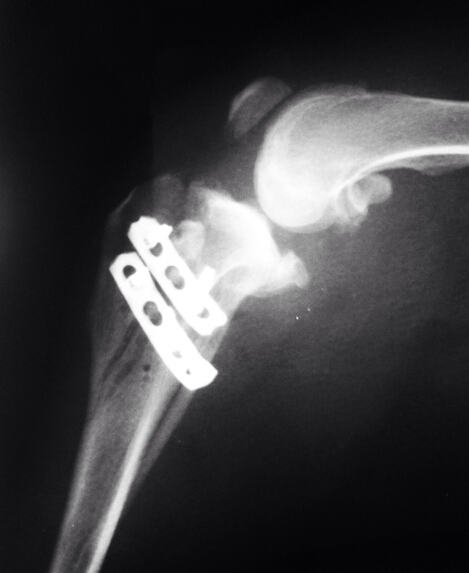

膝关节x光

术前,我们的冼医生为之进行了简单的理学检查。我们重新拍摄了膝关节x光,计算了手术的植入物宽度。准备好之后,我们开始对动物麻醉,上了监护。在消毒好,我们手术开始了十分钟之前,任麻醉师的冼医生示意让我停止手术。我不解,但必须听指挥。要知道,手术中最高权力者非主刀医师,而是麻醉师。